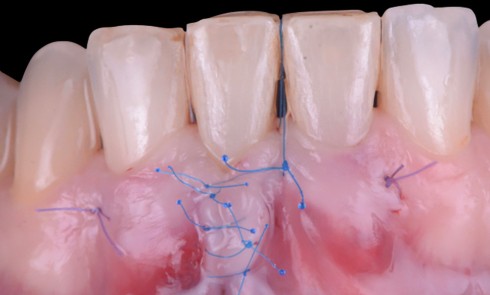

La greffe de tissus mous comme facteur préventif

La greffe vestibulaire de tissus mous agit donc comme un facteur préventif dans l’apparition de déhiscence des tissus mous péri-implantaires.

De plus, l’étude de Jung et al. [2] a montré qu’une épaisseur de tissus mous importante est garante d’un résultat esthétique satisfaisant et que la greffe de tissu conjonctif demeure le gold standard en matière de gain d’épaisseur tissulaire. Il convient donc de se tourner vers ce type de greffon.

Ce tissu conjonctif peut être prélevé soit au palais, soit à la tubérosité. Comme le montre…